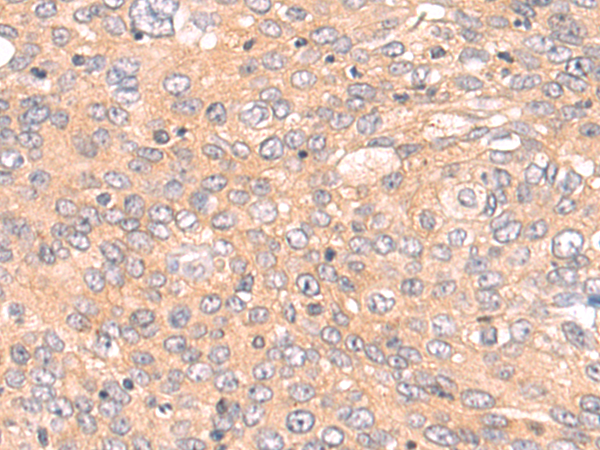

分类: 科研抗体货号: P08707别名: ARHE; Rho8; RhoE; memB应用: IHC反应种属: Human, Mouse, Rat